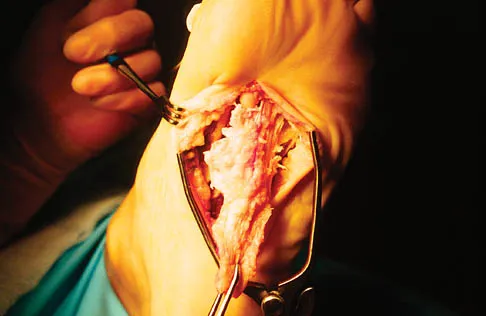

A 16-year-old girl has a painful foot mass. A radiograph, MRI scan, and biopsy specimens are shown in Figures 35a through 35d. What is the most likely diagnosis?

Synovial sarcoma should always be considered in the differential diagnosis of a foot mass; however, the histopathology shows a typical example of PVNS, with hemosiderin, giant cells, and synovium. Synovial chondromatosis would have metaplastic cartilage in the synovium. The radiograph shows subtle erosion of the lateral cortex of the cuboid, and the MRI scan shows a soft-tissue mass. Ghert MA, Scully SP, Harrelson JM: Pigmented villonodular synovitis of the foot and ankle: A review of six cases. Foot Ankle Int 1999;20:326-330. Jones BC, Sundaram M, Kransdorf MJ: Synovial sarcoma: MR imaging findings in 34 patients. Am J Roentgenol 1993;161:827-830. Sartoris DJ, Resnick D: Magnetic resonance imaging of pediatric foot and ankle disorders. J Foot Surg 1990;29:489-494.